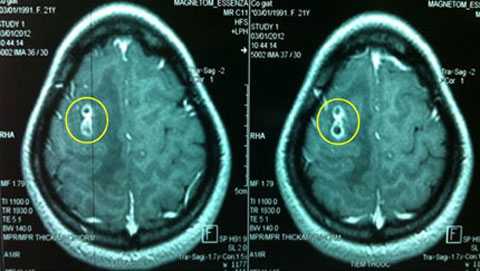

Chị Lan Hương đã vào BV Bạch Mai khám. Kết quả chụp MRI (cộng hưởng từ) sọ não và làm các xét nghiệm cho thấy não bị tổn thương nhưng không phải do khối u mà là do giun đũa chó gây nên.

| Hình ảnh chụp MRI của bệnh nhân Lan Hương (ảnh do bác sỹ cung cấp) |